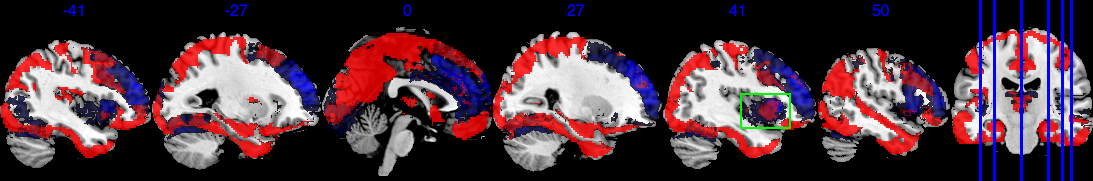

In addition, Figure 6 shows results equivalent to those in Figure 3, but with the selection indicator applied simultaneously to both the main effect and the interaction effect. As shown in Figure 6(b), the posterior of in model (10) is driven by both and . The regions exhibiting strong negative effects of do not fully align with the regions showing , in contrast to the original results in Figure 3(b). Therefore, if the primary interest is in the main exposure variable , such as age in our analysis, we recommend applying exclusively to this primary effect to achieve a more accurate selection of activation regions.

Since the gender variable is binary with female being 0 and male being 1, the interpretation for is that comparing to the female subjects, one standard deviation (s.d.) increase in age for male subjects is associated with -s.d. of change in the image intensity. The boxed green area in Figure 6(c) and Figure 6(b) identifies one active area where has a negligible effect, but has a large effect size, indicating that this area is associated with the differences of male’s age-brain intensity association compared to female. For example, one s.d. increase in male’s age is associated with at least 0.01 s.d. increase in brain signal intensity compared to the female baseline in this green-boxed area. On the other hand, Figure 6(d) also identifies areas where one s.d. increase in male’s age is associated with at least 0.01 s.d. decrease in brain signal intensity compared to the female baseline. The area in the green box spans several brain regions in the right hemisphere, including Right lateral occipital cortex, superior division, Right insular cortex, Right middle temporal gyrus, posterior division, and Right frontal operculum cortex. They jointly integrate information from multiple modalities and detect behaviorally relevant stimuli. The negative in Figure 6(d) spans over Right parahippocampal gyrus, posterior division, Right temporal fusiform cortex, posterior division, Left temporal fusiform cortex, posterior division, Left temporal pole. They jointly process and integrate vision and semantic information and are related to contextual and memory functions.